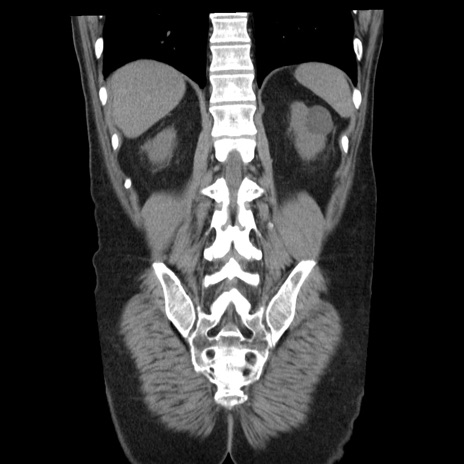

症例29(冠状断像)

【症例】40歳代男性

【現病歴】2日前から胃痛あり。徐々に周期的な激痛に変化した。本日になっても激痛があるため受診。

【身体所見】意識清明、BT 38-39℃台あり、腹部:膨満、やや硬、右下腹部に圧痛あり。

【データ】WBC 8500、CRP 23.26